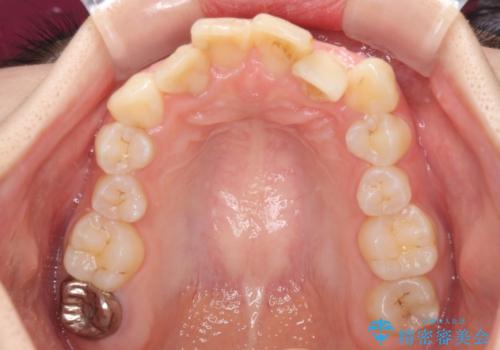

デコボコと深い咬み合わせ ワイヤー装置での抜歯矯正

- 内側に倒れ込んだ歯や下の前歯が隠れてしまうほどの咬み合わせを改善したいとのことで来院された患者様です。

下顎の叢生を解消するために抜歯が必要であり、奥歯の咬み合わせや口元の印象から、上顎も同様に抜歯と判断し、上下左右の第1小臼歯4本抜歯してワイヤー装置にて矯正治療を行うこととしました。

咬み合わせが深く、そのままでは上顎の抜歯スペースが閉じきらない可能性があったため、治療初期から深い咬み合わせを改善させるように試みました。

実際にはなかなか改善されず、当初予定よりも治療期間がやや長期化してしまいました。